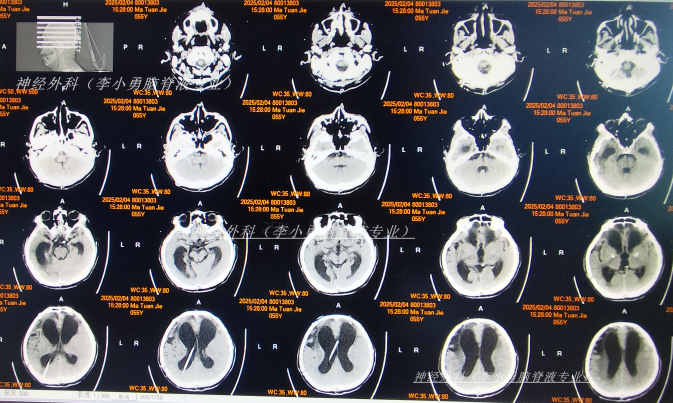

2025年2月4日(脑外伤术后8个月,脑积水分流术后138天即颅骨修补术后110天,反复发热2月半),转至李小勇脑脊液专业,入院时:昏迷,上肢刺痛后稍有反应,下肢刺痛无反应;体温间断发热,双瞳孔对光反射迟钝;口腔内气管插管,鼻饲流食;大小便不能自理(图-11)。

入院当天查头颅CT示颅脑术后改变,脑室扩张,双侧额部硬膜下积液(图-12);胸部CT示两肺炎性病变,心包积液,双侧胸腔积液(图-13)。

图-12:2025年2月4日头颅CT

图-14:2025年2月4日术后头颅CT